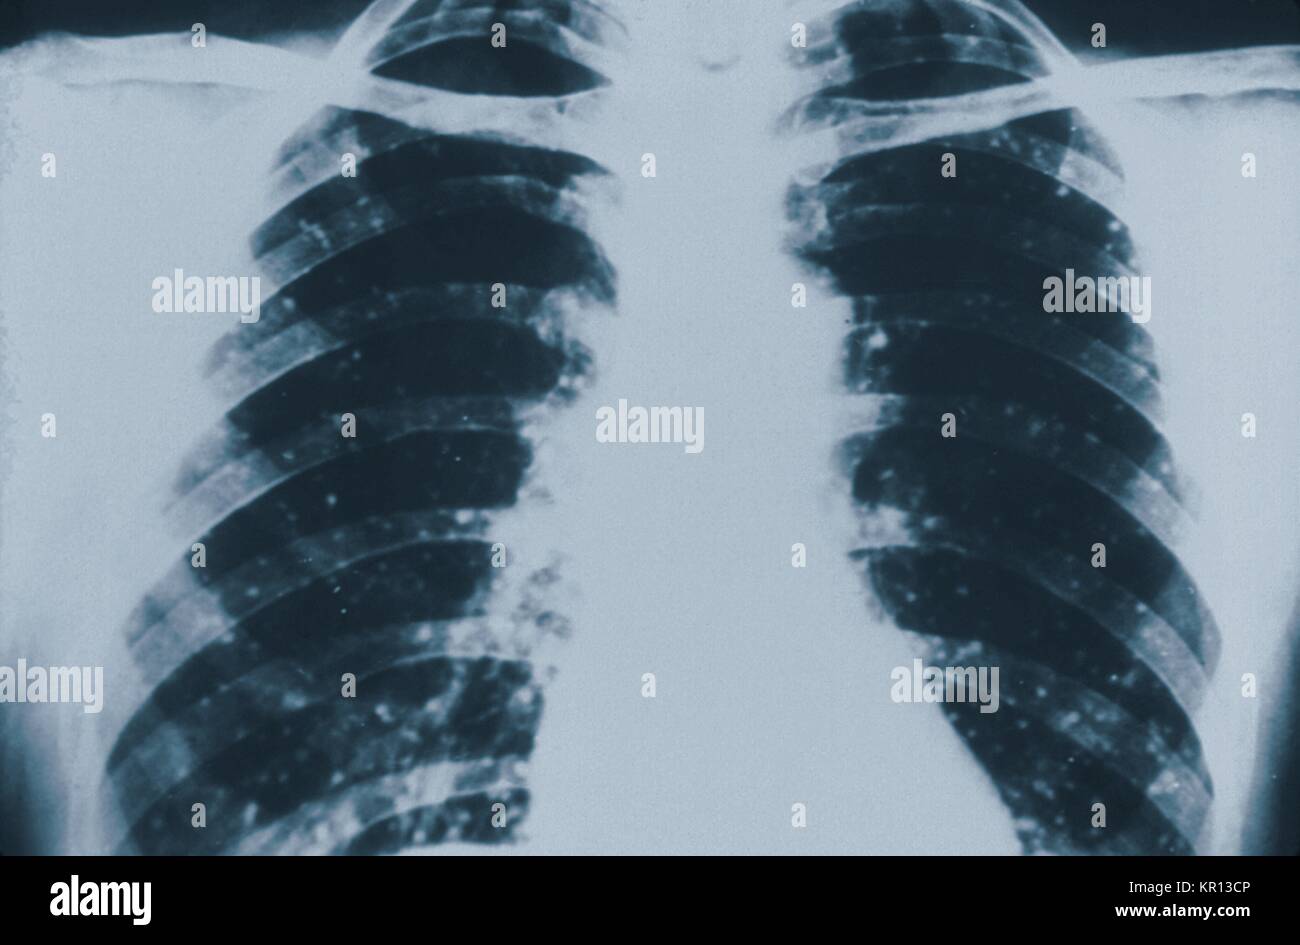

This anteroposterior (AP) chest xray revealed the presence of numerous Millet Seed X Ray Widespread hematogenous dissemination of mycobacterium tuberculosis. Miliary tuberculosis is a severe form of tuberculosis (tb) caused by the dissemination of mycobacterium tuberculosis bacteria throughout. Miliary tuberculosis is a rare form of tuberculosis that affects the lungs and other organs. So named because the nodules are. Learn how to identify and differentiate the four patterns of interstitial lung disease (ild) on. Millet Seed X Ray.

(A) Millet seeds appearance of the lungs due to miliary tuberculous Millet Seed X Ray Learn about its pathology, radiographic features,. So named because the nodules are. Miliary tuberculosis is a severe form of tuberculosis (tb) caused by the dissemination of mycobacterium tuberculosis bacteria throughout. It is useful to divide these. Widespread hematogenous dissemination of mycobacterium tuberculosis. Learn how to identify and differentiate the four patterns of interstitial lung disease (ild) on chest radiographs and. Millet Seed X Ray.